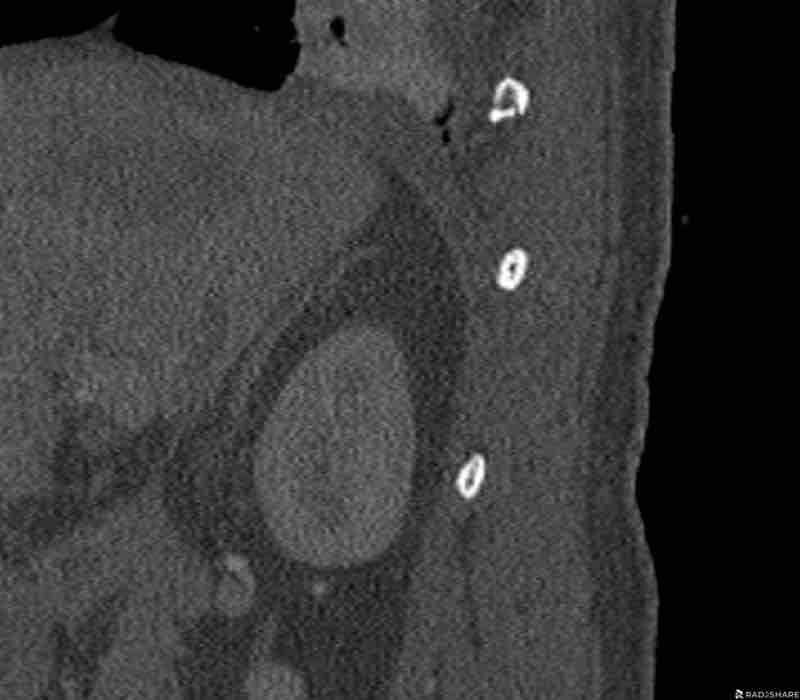

Scroll through images.

What are the findings?

Findings

- C injury? No.

- Signs of a rigid spine?

Yes, a B3 injury is very likely. - A subtle fracture on the anterior vertebral body.

Conclusion

Injury type B3.